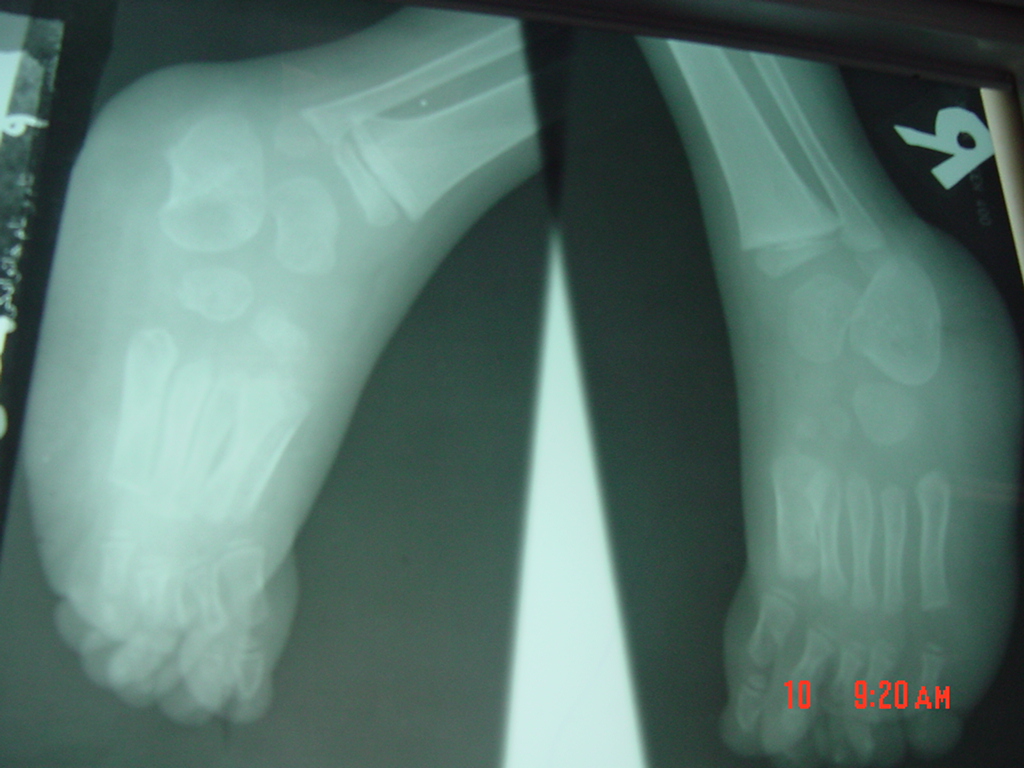

این عمل در مرکز جراحی ولنجک و زیر نظر دکتر حقانی فوق تخصص دست صورت گرفته

تاریخ عمل  پنج شنبه 20 شهریور 1393

شست کوتاه